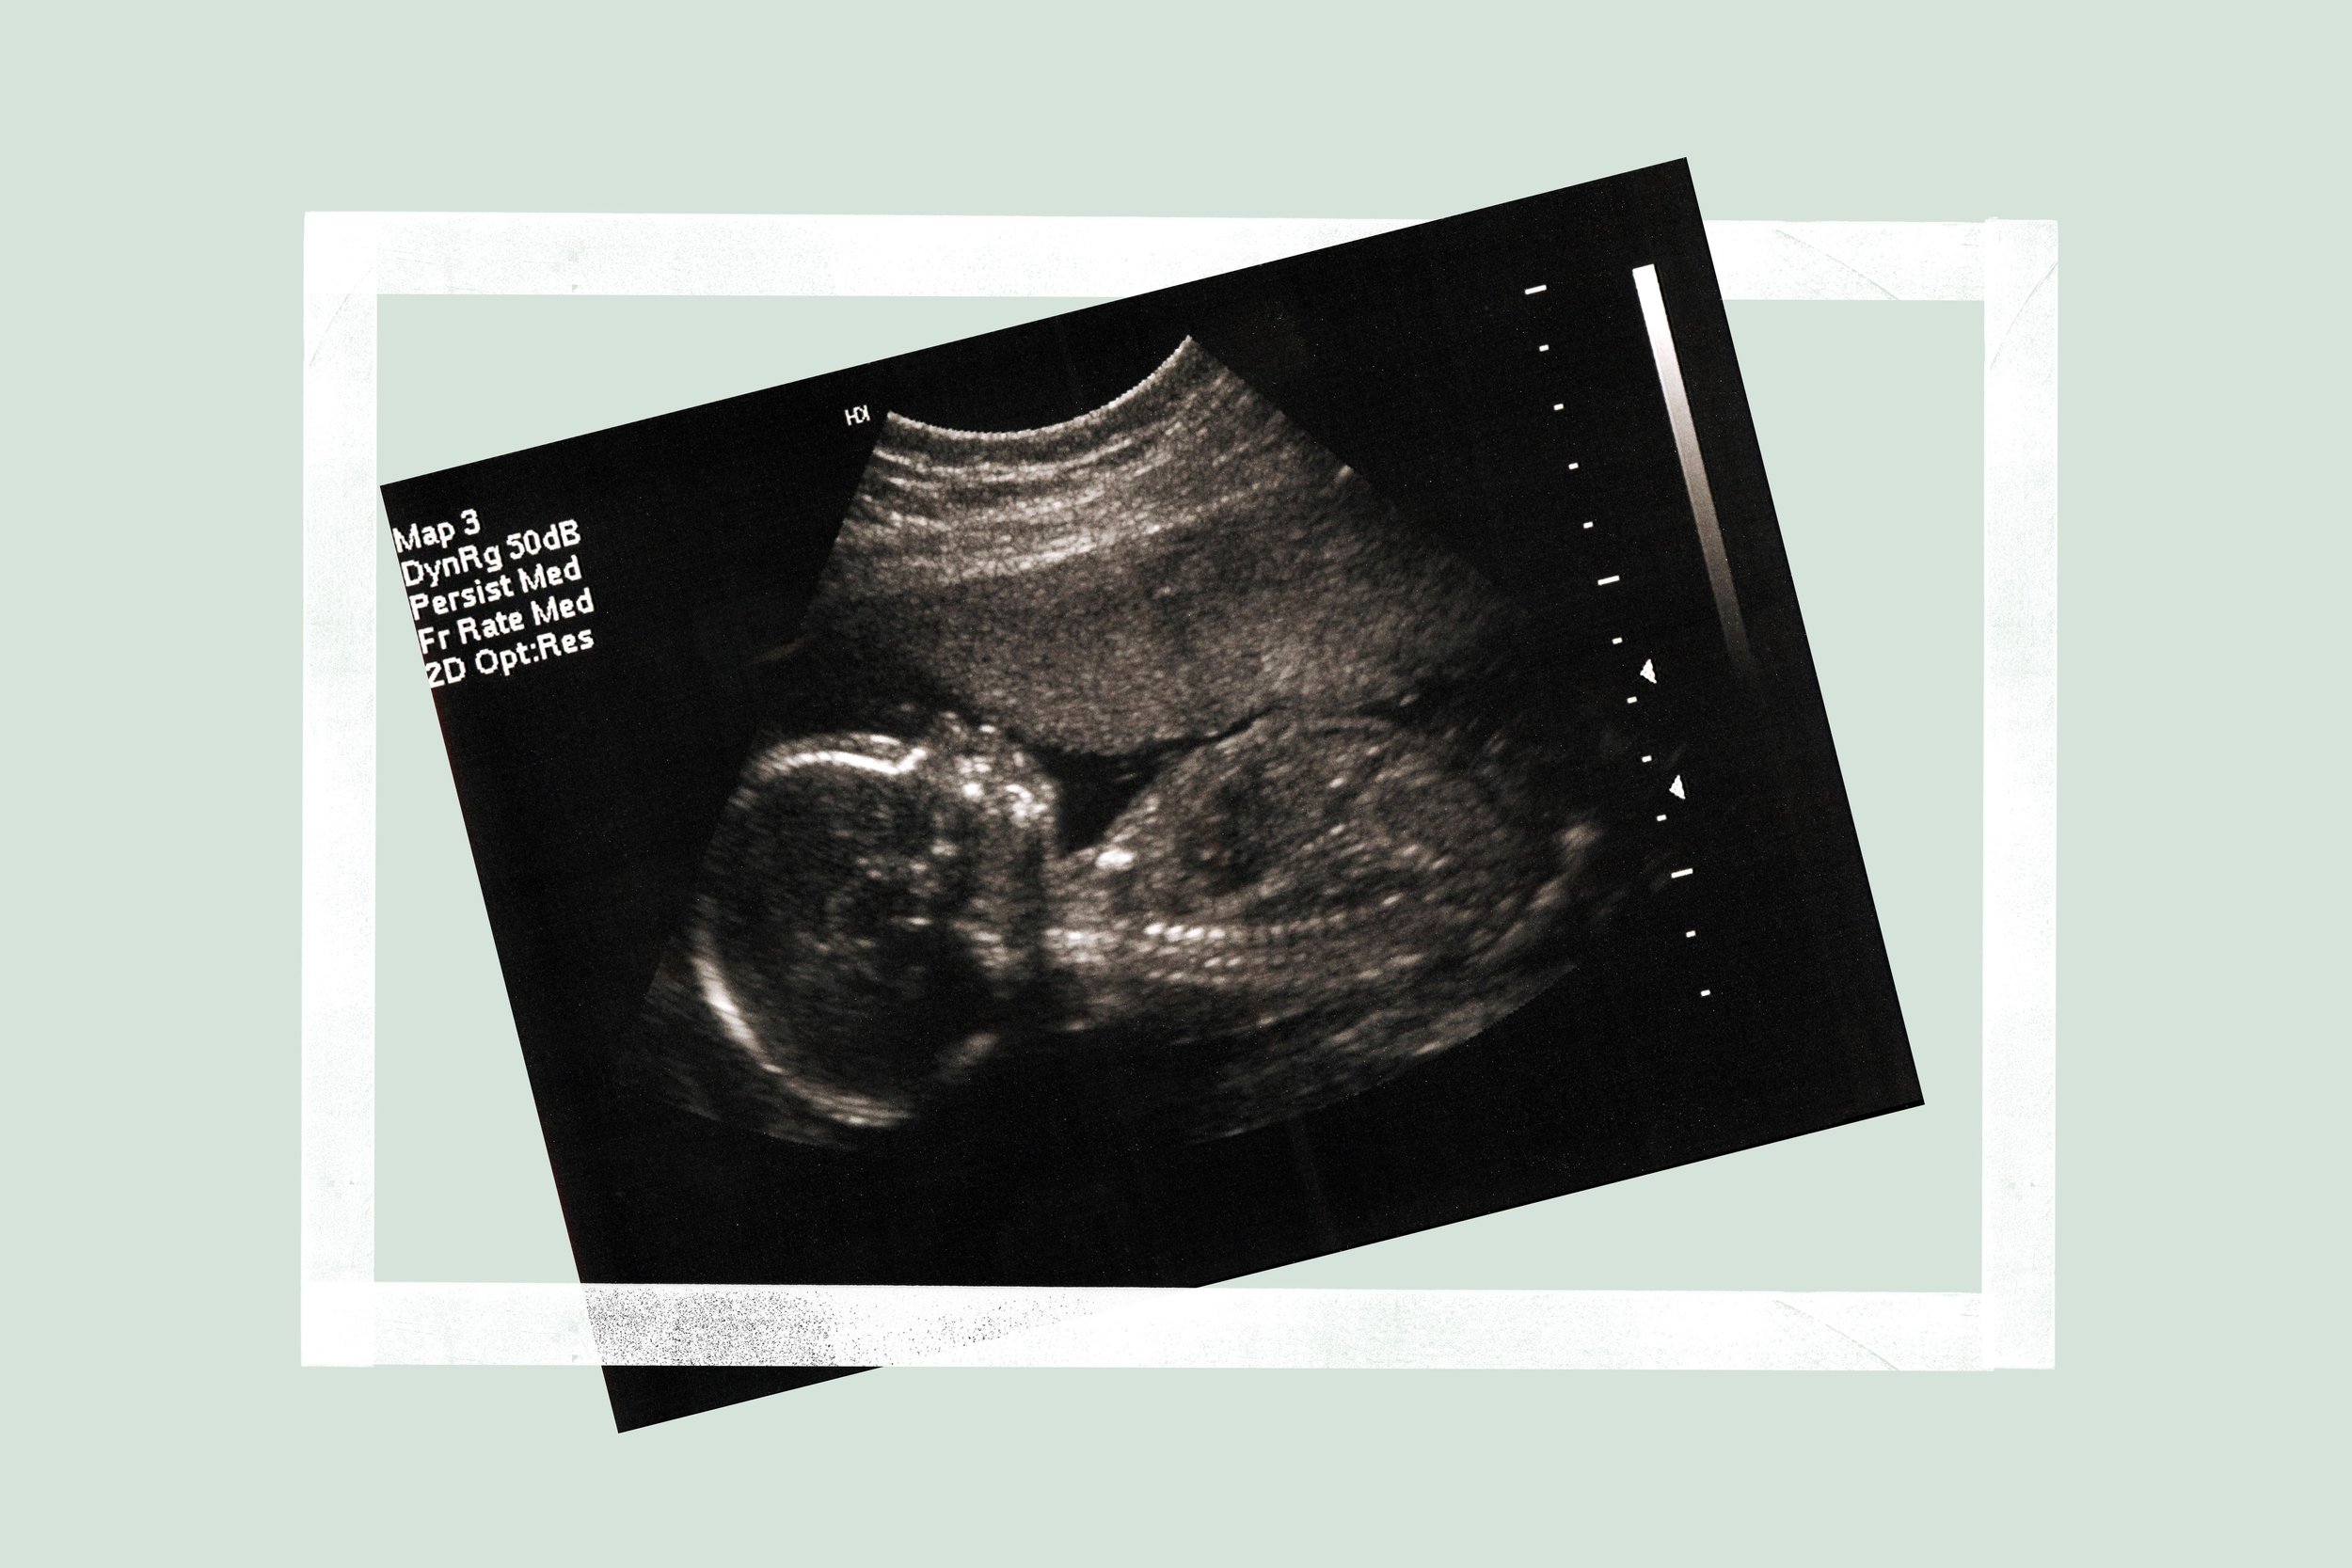

Preparing for the 20 week scan

You’ve almost reached the halfway mark and in the next week or so you’re going to have the opportunity to see your baby again!

The 20-week scan is a detailed scan of your baby’s physical development – it looks at your baby’s bones, heart, brain, spinal cord, face, kidneys and abdomen. It also looks at the placenta, blood flow and fluid surrounding your baby.

The person performing the scan will also check your baby’s genitals so this is the chance to find out the sex of you baby if you haven’t already and would like to.

The length of your baby as well as their head and tummy circumference will also be plotted on a graph to monitor how they are growing.

The 20-week scan screens for a number of rare conditions and that is why it is also known as the anatomy or anomaly scan. You will be told at the end of the scan if any further follow up is recommended.

You’ll be given more photos of your baby and you can then compare them to the 12-week ones and see how much they’ve changed and grown!